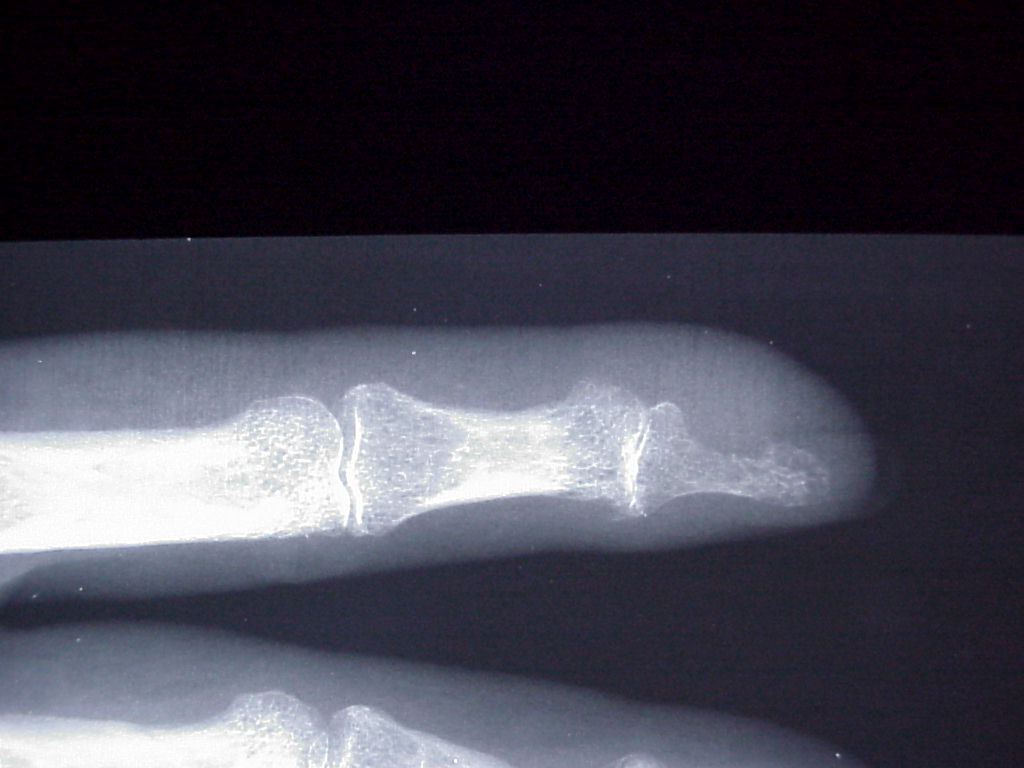

Breast cancer is known to metastasize widely. This patient with poorly differentiated breast cancer developed a fingertip mass. Biopsy confirmed metastasis, but she declined further surgery.

Probable erosive changes of adjacent distal phalanx.